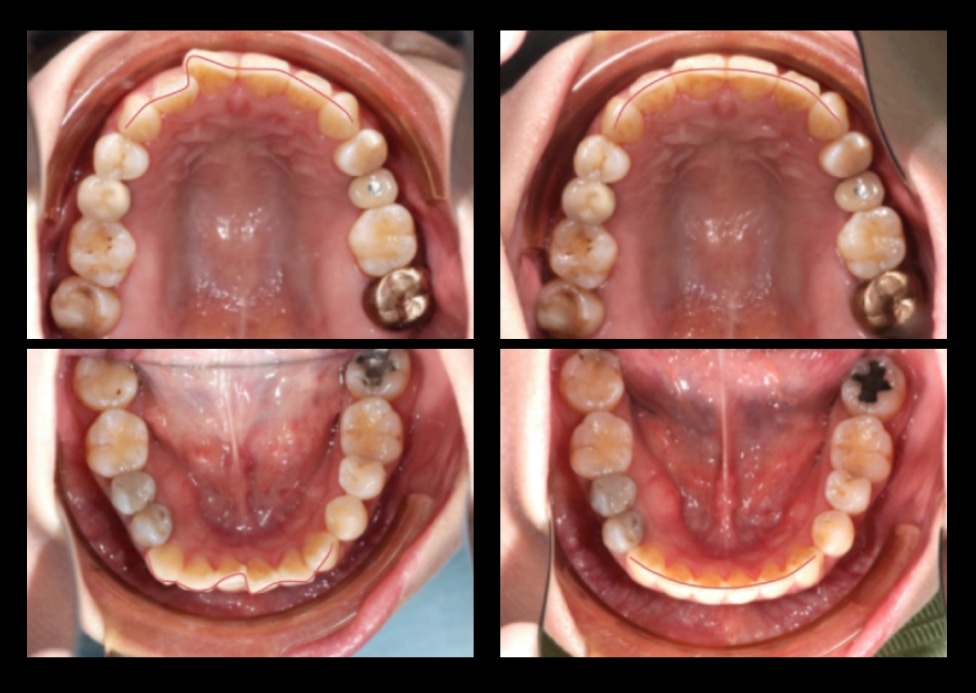

case 4. 牙齒凌亂(拔牙矯正)

• 主訴:牙齒凌亂度高、上排高犬齒、上下排牙齒中線未對齊、右下第二小臼齒舌側偏移

• 治療方式:拔除上下四顆小臼齒,利用小臼齒的空間將牙齒排整齊,並且修正上下中線偏移以達到對稱效果。